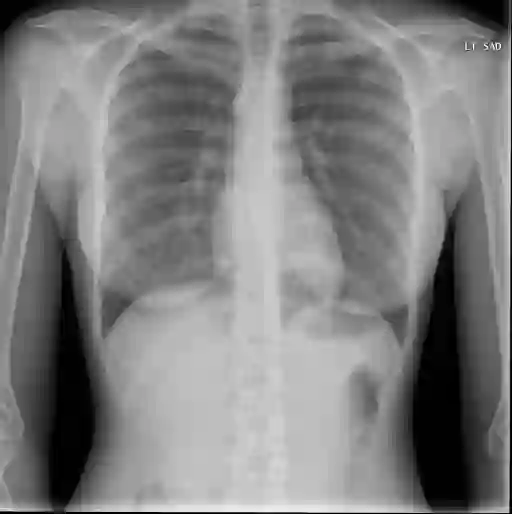

Medical imaging plays a pivotal role in diagnosis and treatment in clinical practice. Inspired by the significant progress in automatic image captioning, various deep learning (DL)-based methods have been proposed to generate radiology reports for medical images. Despite promising results, previous works overlook the uncertainties of their models and are thus unable to provide clinicians with the reliability/confidence of the generated radiology reports to assist their decision-making. In this paper, we propose a novel method to explicitly quantify both the visual uncertainty and the textual uncertainty for DL-based radiology report generation. Such multi-modal uncertainties can sufficiently capture the model confidence degree at both the report level and the sentence level, and thus they are further leveraged to weight the losses for more comprehensive model optimization. Experimental results have demonstrated that the proposed method for model uncertainty characterization and estimation can produce more reliable confidence scores for radiology report generation, and the modified loss function, which takes into account the uncertainties, leads to better model performance on two public radiology report datasets. In addition, the quality of the automatically generated reports was manually evaluated by human raters and the results also indicate that the proposed uncertainties can reflect the variance of clinical diagnosis.

翻译:医学成像在临床实践的诊断和治疗中发挥着关键作用。在自动图像说明的重大进展的启发下,提出了各种基于深层次学习(DL)的方法,为医疗图像生成放射学报告。尽管取得了令人乐观的成果,但先前的工作忽略了模型的不确定性,因此无法为临床医生提供生成的放射学报告的可靠性/信心,以协助其决策。在本文件中,我们提出了一个新颖的方法,以明确量化基于DL的放射学报告的视觉不确定性和文字不确定性。这种多模式的不确定性可以充分捕捉报告层面和句子层面的模型信任度,从而进一步利用这些方法来权衡损失,以进行更全面的模型优化。实验结果表明,拟议的模型不确定性定性和估算方法能够为生成放射学报告提供更可靠的信心分数,以及考虑到不确定性的修改后的损失功能,使两个公共放射学报告数据集的模型性表现更好。此外,自动生成的报告的质量由人手动评估,结果还表明,拟议的不确定性可以反映临床诊断的差异。